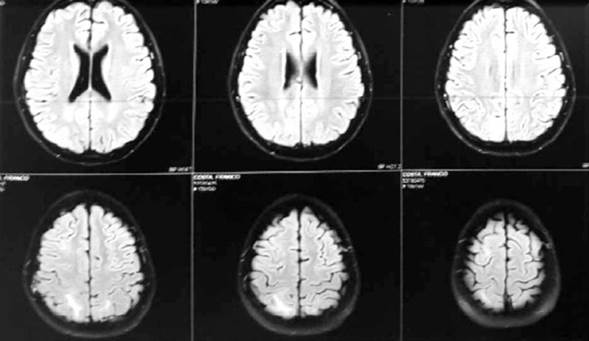

En todos los pacientes, el primer estudio de imagen solicitado fue la TC de cráneo y los hallazgos fueron imágenes hipodensas córtico-subcorticales occipitales, parietales o frontales. Se realizó RM en dos casos mostrando áreas de señal anormal subcorticales parietales posteriores bilaterales. Hiperintensas en T2 y Flair. hipointensas en T1, sin restricción de la difusión (Figura 1).

Figura 1: Resonancia magnética correspondiente al caso 4, donde se evidencian áreas de señal anormal subcorticales parietales posteriores bilaterales. Hiperintensas en T2 y Flair. Hipointensas en T1, sin restricción de la difusión.